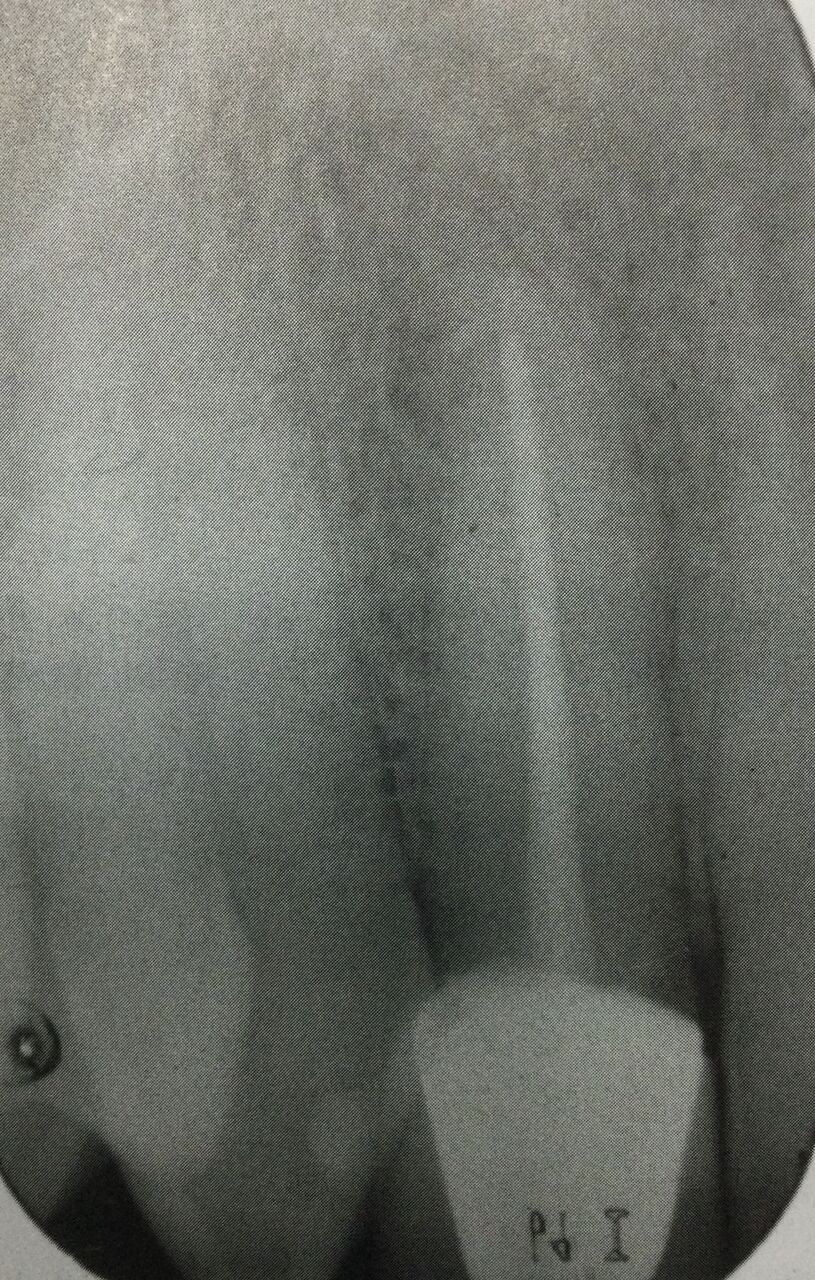

この歯の治療方法は?

●根管治療をやり直して、被せ物も新しくする。

●外科的に根っこの先を治療する。

●抜いちゃって、インプラントかブリッジか入れ歯にする。

●何もしない。

相談した後、患者さんは再根管治療を希望された。

今入っている被せ物を外して残っている健康な歯の量を診てみないと、被せ方は決められないと説明しました。

なんで被せ物を外さないとならないんですか?

●後で被せ直せそうなのか?を調べるために、残っている歯の量を知るのに。

●特に隙間がある時、中に虫歯ができていないのか?を調べるため。

●被せ物の形は元々のものとは同じではないので、神経へと削る際に必要以上に穴が大きくなるのを防ぐため。

●神経への道作りを直線的に行うのに、被せ物が邪魔にならないように。

● 最も適切な被せ方を決めるためには、残っている歯を評価しないとなりません。